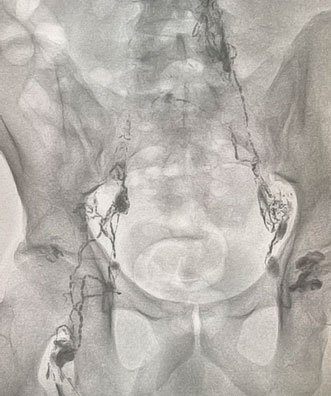

Chylous leak

Dye travelling upwards from lymph nodes

Lymphangiography showing leak